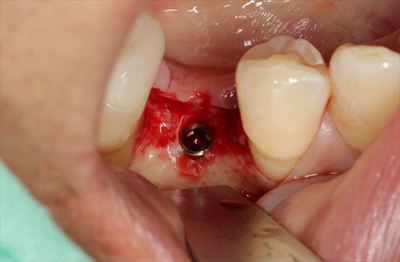

挿入ジグを外しました。

封鎖スクリューでインプラントフィクスチャーのスクリューホールを封鎖します。

封鎖しました。